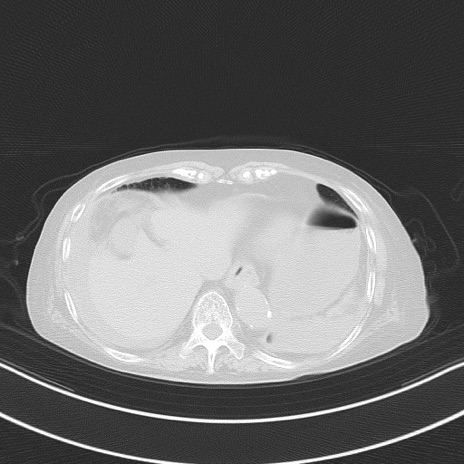

横断像